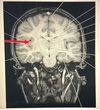

9

Q

A. Epidural hematoma

B. Subarachnoid hemorrhage

C. Intracerebral hemorrhage

D. Subdural hematoma

A